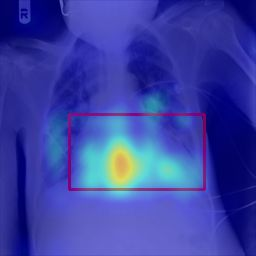

Deployments of artificial intelligence in medical diagnostics mandate not just accuracy and efficacy but also trust, emphasizing the need for explainability in machine decisions. The recent trend in automated medical image diagnostics leans towards the deployment of Transformer-based architectures, credited to their impressive capabilities. Since the self-attention feature of transformers contributes towards identifying crucial regions during the classification process, they enhance the trustability of the methods. However, the complex intricacies of these attention mechanisms may fall short of effectively pinpointing the regions of interest directly influencing AI decisions. Our research endeavors to innovate a unique attention block that underscores the correlation between 'regions' rather than 'pixels'. To address this challenge, we introduce an innovative system grounded in prototype learning, featuring an advanced self-attention mechanism that goes beyond conventional ad-hoc visual explanation techniques by offering comprehensible visual insights. A combined quantitative and qualitative methodological approach was used to demonstrate the effectiveness of the proposed method on the large-scale NIH chest X-ray dataset. Experimental results showed that our proposed method offers a promising direction for explainability, which can lead to the development of more trustable systems, which can facilitate easier and rapid adoption of such technology into routine clinics. The code is available at www.github.com/NUBagcilab/r2r_proto.